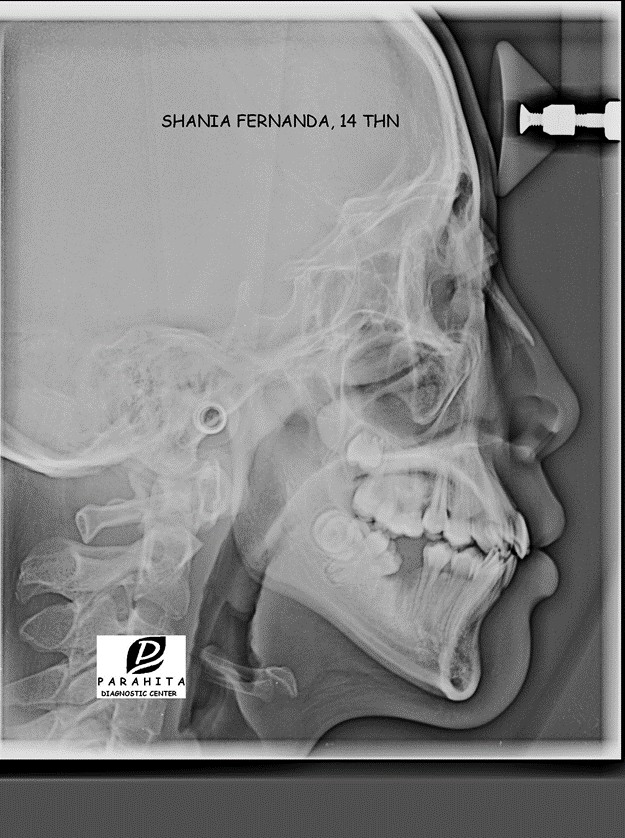

Figure 3. Foto sefalometri

Berdasarkan foto panoramic(gambar 4) ditemukan impaksi gigi pada 18 dan 28. Perhitunga sefalometri menunjukan skeletal kelas I dengan ANB 3º. Relasi gigi didapatkan bahwa inklinasi gigi rahang atas normal (I-NA 20º) dan gigi rahang bawah normal (I-NB 24º) dan terdapat rotasi mandibula ke bawah dan ke belakang (Gbr.3). Analisis jaringan lunak menunjukkan bahwa bibir atas dan bawah menonjol (Tabel 1). Berdasarkan dari anamnesa dan pemeriksaan klinis dimungkinkan bahwa etiologi maloklusifaktor herediter.